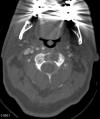

Pathologic fractures involving the C2 vertebral body and odontoid process pose a unique dilemma, as the surgical approach for direct odontoid process screw fixation has several limitations. There have been a small number of transoral approach C2 vertebroplasty or kyphoplasty reported in the literature. Previous attempts were performed utilizing fluoroscopy or CT guidance. We report a case of a fluoroscopically guided transor-al approach vertebroplasty in a patient with a lytic lesion involving the C2 vertebral body, extending into the odontoid process with an underlying pathologic fracture. This case is unique as two separate punctures were required in order to adequately stabilize the pathologic fracture, CTA was performed preoperatively to better evaluate regional vasculature, and a post-procedure rotational flat panel CT was performed to assess cement placement.